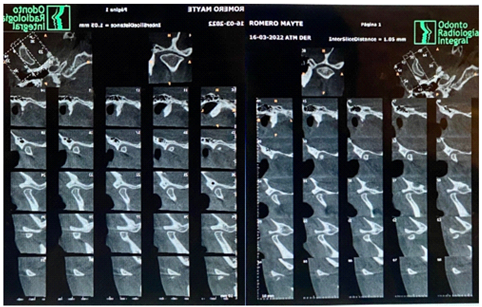

Following are images of the right and left TMJs of Dr. Marcelo Mochó's patient A.A. as an example of the studies performed at the Institute, where no particularities were observed in the TMJs (Figure 13). Also shown is the control tomography of patient M.R. after 5 years of treatment. The condyles are slightly flattened (Figure 14).